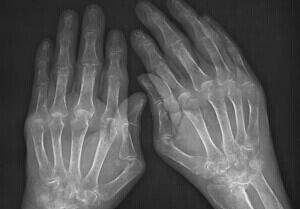

来院后,我院类风湿医生杜爱华主任立即为高女士安排检查。检查后发现高女士双手的近端还有指间及关节处会有关节肿胀的现象,并且双腕肿胀现象比较严重,下蹲困难,活动受限;最后确诊为类风湿性关节炎。

(图:体查、X线片检查都显示高女士类风湿病情严重)